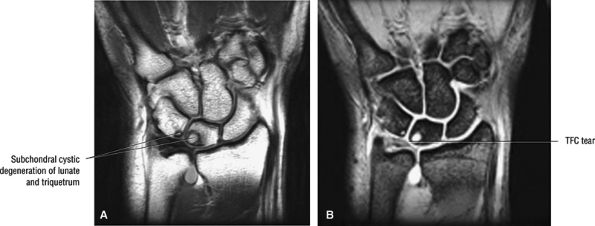

![]() |

FIGURE 10.55